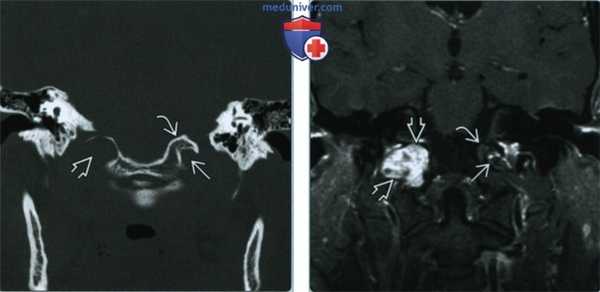

По данным МРТ головного мозга с усилением сигнала парамагнетиком выявлена опухоль парастволовой локализации справа, компримирующая продолговатый мозг и исходящая из расширенного канала подъязычного нерва. Меньший по размерам компонент опухоли располагался в полости канала и распространялся экстракраниально (рис. 1). Рис. 1. МРТ головного мозга пациентки В. до операции. При усилении сигнала выявляется опухоль справа, соответствующая невриноме, в форме «гантели», располагающаяся одной частью на уровне краниовертебрального перехода и вызывающая компрессию ствола мозга, а другой — частью в костных структурах.

(Слева) При корональной КТ в костном окне наблюдается значительное расширение правого канала подъязычного нерва и эрозия нижней поверхности «орлиного клюва». Сравните наблюдаемую картину с левым каналом подъязычного нерва и яремным бугорком.

(Справа) При МРТ Т1 FS с КУ в корональной проекции у этого же пациента наблюдаются неравномерное контрастирование шванномы, выраженная фестончатость прилегающей затылочной кости и облитерация нормального «орлиного клюва»; те же изменения наблюдаются и на КТ. Слева определяются нормальный канал подъязычного нерва и яремный бугорок.